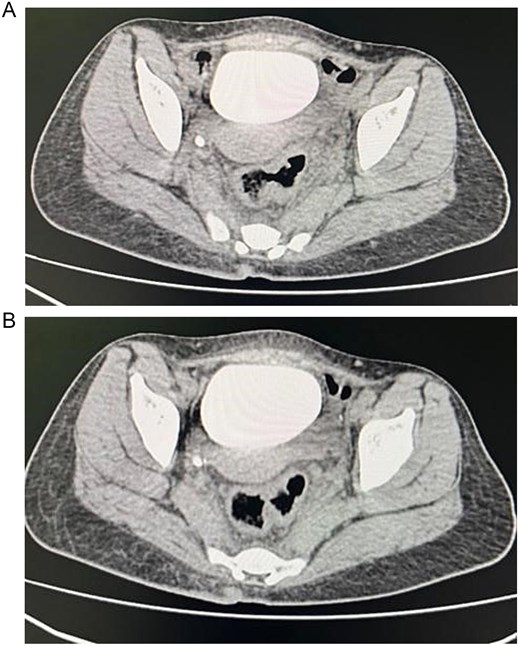

Computed tomography (CT) abdomen and pelvis showed perforated sigmoid diverticulitis, extraluminal collection measuring 3 × 1.8 cm, fistula formation extending to left aspect of urinary bladder dome, and another fistula possibly extending to anterior wall of rectum (Fig. 1).

(A) Axial section of the abdominopelvic CT scan showing the colovesical fistula. (B) Axial section of the abdominopelvic CT scan showing the diverticular disease of the colon.